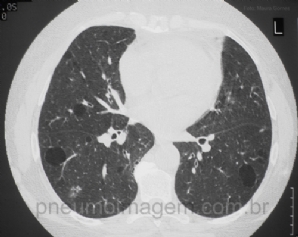

CASO CLÍNICO #7

Paciente do sexo feminino, 30 anos, que apresenta dispneia aos esforços e poucos sintomas gerais, além da sensação olho seco. Qual o diagnóstico mais provável? Deixe os seus comentários abaixo! ***** Female patient, 30, who has dyspnea on exertion and a few ...